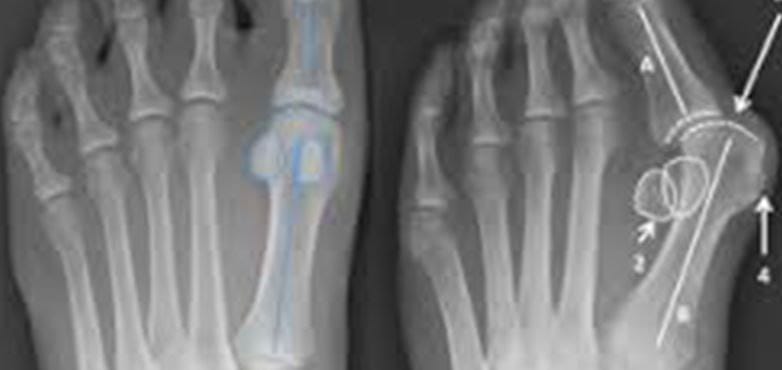

- Foot and ankle.

- Foot & Ankle